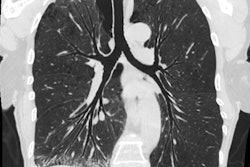

Lung imaging software developer Vida Diagnostics has inked a deal with the University of Iowa Hospitals and Clinics.

The vendor said it will provide its clinical imaging software and analysis services in support of lung cancer screening, interventional pulmonology, and other precision healthcare efforts at the institution.